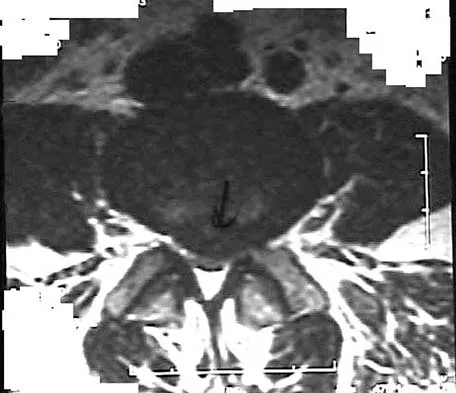

A 60-year-old man is evaluated in the ICU after a rollover motor vehicle accident 3 days ago. He has multiple upper and lower extremity trauma and was found unresponsive at the accident scene. Surgery is planned for the extremity trauma once the patient is medically stable. He remains intubated and the cervical spine is immobilized in a semi-rigid collar. Examination reveals mild erythema in the posterior occipital cervical region. Initial AP and lateral radiographs of the cervical spine have not revealed any obvious fracture. What is the most appropriate treatment option at this time?